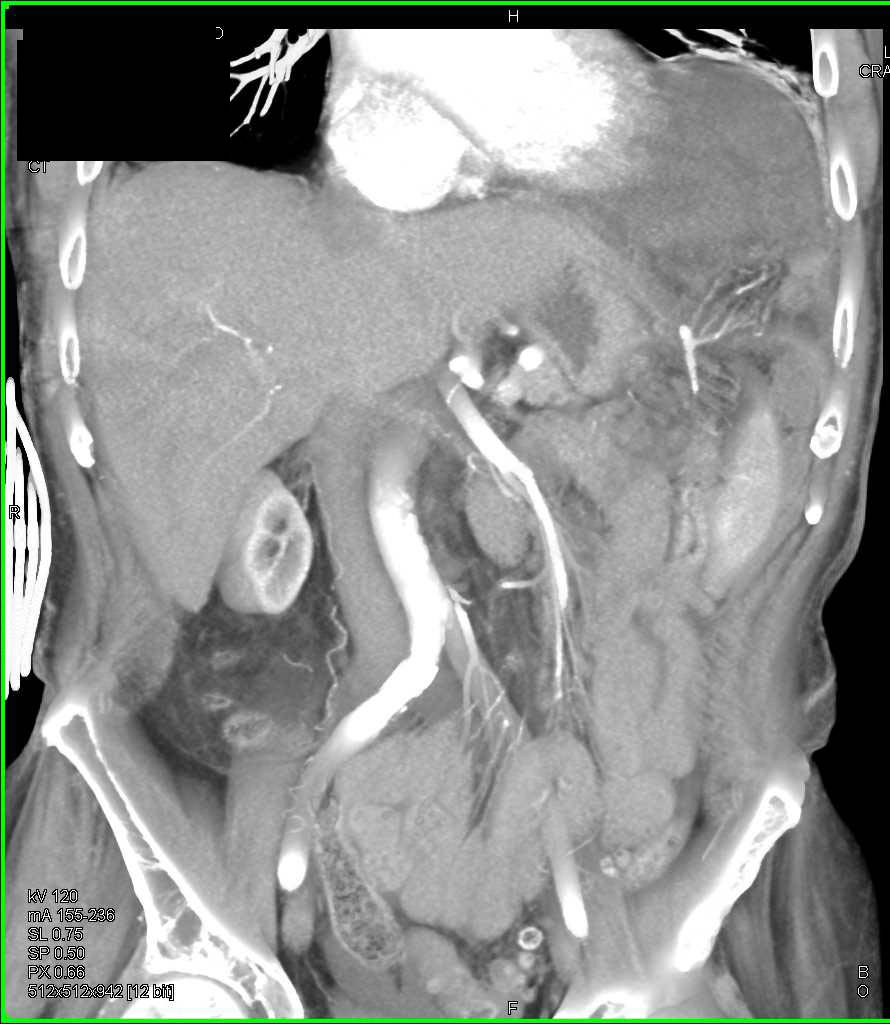

Bladder Perforation with Intraperitoneal Contrast Extravasation